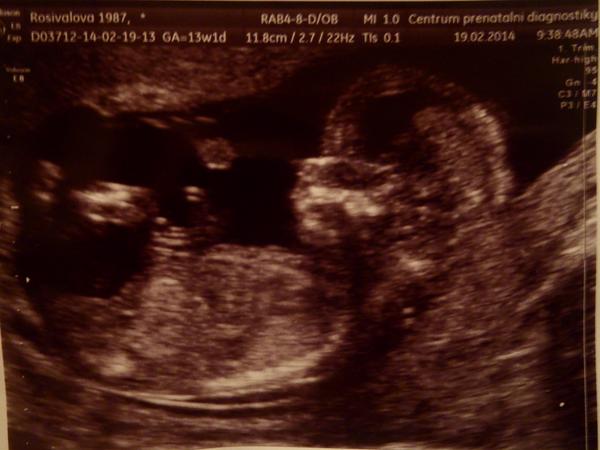

@makiska1 moc gratuluji!!!!!!! je krásná!!!!!!! 😵 😵 úplná modelka 🙂 a ukazovala se doktorovi hned? nebo na něho nohy neroztahovala? 😀 😀 kámoška byla na NT dva měsíce zpátky a první co malá ukazovala, byl rozkrok 😀 jsem jí říkala, že jí pak bude muset v pubertě hlídat 😀 jo utz doma by nebyl od věci......ale já bych pak nic jinýho nedělala 😅 😅

@makiska1 hele tak to naše miminko bude asi ošklivý po mamince, když mám fotku zadarmo 😀 😀 chuďátečko moje.......já ho nedám!!! 😀

chjoo holky, já bych nejradši šla zas na nějaký utz, abych ho viděla, toho našeho prcka vymodlenýho 🙂